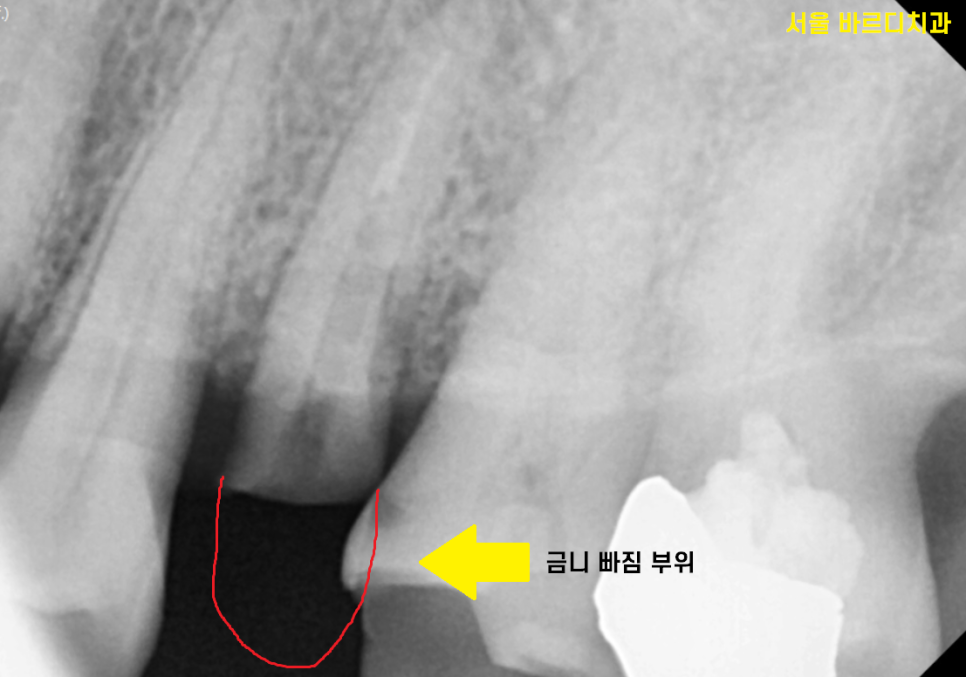

23.11.14

치아 부러진 부위가 너무 커서

발치할 수 밖에 없었는데요.

아무리 보강을 해서 새로 만들어 드려도

치아의 씹는 힘은

어금니의 경우 700kg 정도의 힘을 받습니다.

때문에 비용을 들이고

시간을 들여 치료하였을 때

오래 못쓸꺼 같으면

발치하고 미사 임플란트 하는 쪽으로

상담을 진행해드리고 있습니다.

치아가 부러져서 뽑는 경우에는

잇몸뼈가 좋기 때문에

바로 임플란트를 심어드렸습니다.